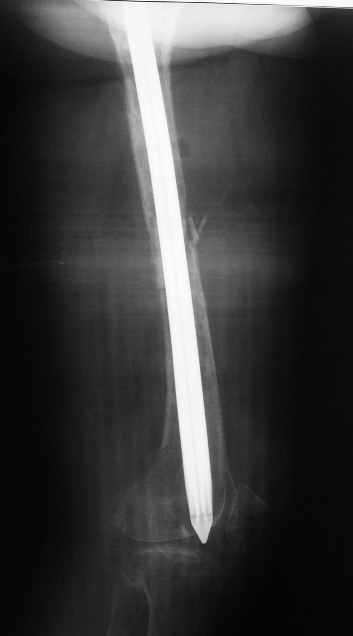

Анамнез: В 2005 году в ЦРБ - остеосинтез перелома бедра пластиной. В 2007 г. воспаление в ср. трети бедра и удаление пластины. Через 2 мес. - рефрактура и фиксация гвоздем "фикшн". Через 2 мес. после синтеза - свищ, "функционирующий" по настоящее время. Что делать?